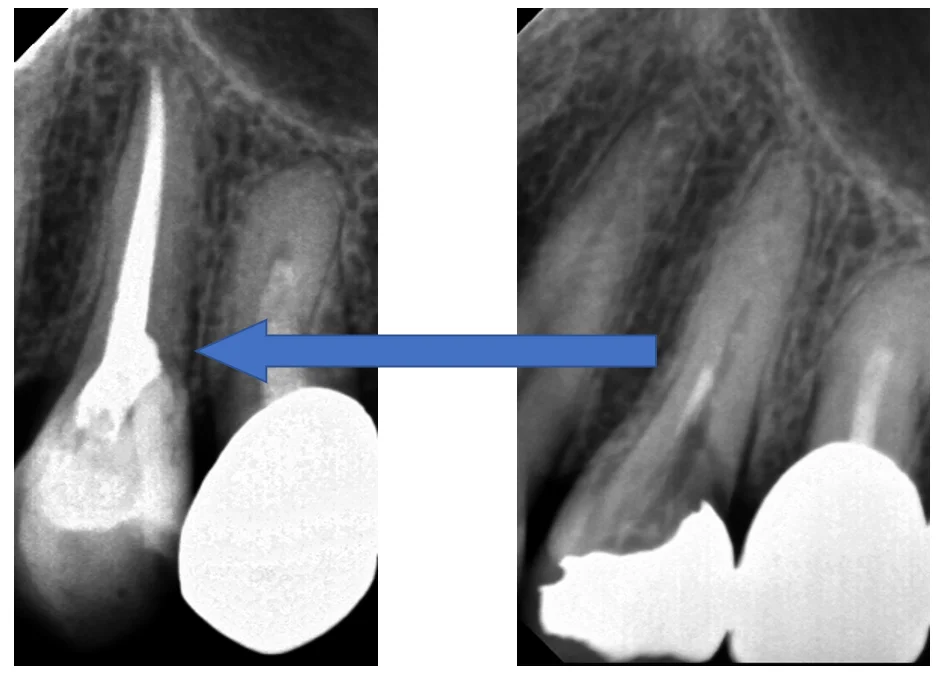

術前術後がこちらですね。

根の先まで隙間なくしっかりと詰まっていて、最初のちょろっとしか入っていなかった薬に比べると随分としっかりと入ったのが分かると思います。